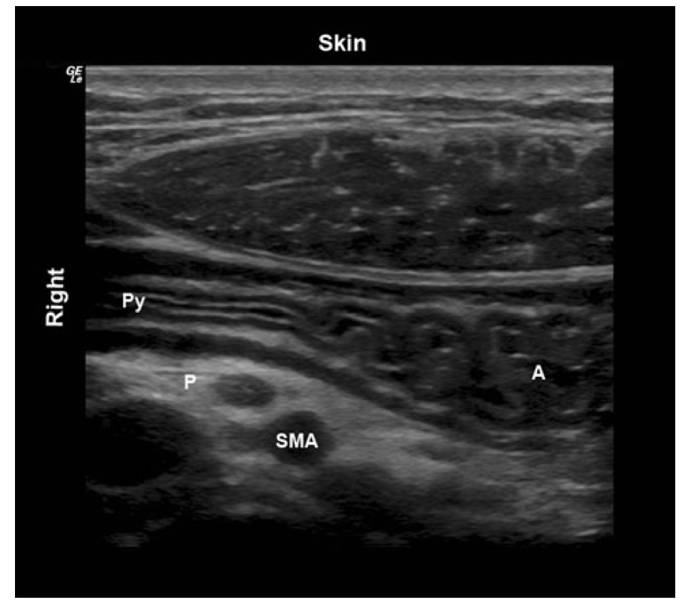

?影像定位:肝左叶、肠系膜上动脉和腹主动脉作为解剖标志

检查平面【1】

胃窦CSA(cross-sectional area) A: 根据测量的胃窦前后径(AP)和头骶径(CC)计算CSA:CSA=(AP×CC×π)/4 B:“自由示踪”法计算CSA